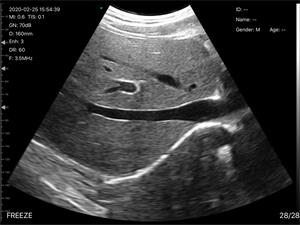

C3无线超声诊断仪

适用对象:

[ 猫、狗、牛、马、老鼠、异宠 ]

数字成像技术,清晰的图像,高性价比

无线连接,操作简单轻便,携带方便